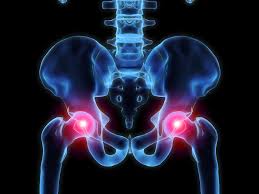

I have a labral tear in my hip, do I need surgery?

The hip joint has been under a lot more scrutiny in the last 15 years with the advent of cheaper and higher quality MRI scans. Patients are increasingly been diagnosed with labral tears as the cause of their symptoms.

But are labral tears normal and do they need treatment? Read more